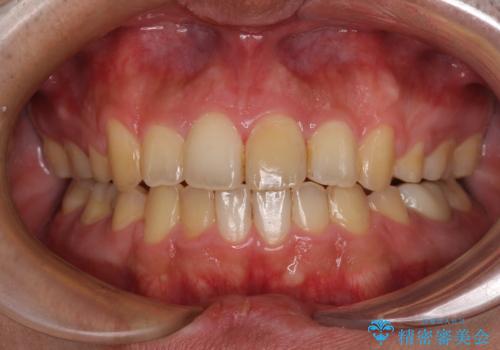

後戻りでデコボコの前歯 インビザライン矯正治療

下顎骨が左側に変位しているため、正中が合わないことは予想できましたが、歯列が整った後も咬み合わせが安定せず、咬み合わせを落ち着かせるために1年以上の期間を要しました。

噛みにくさの改善に時間がかかってしまうことがインビザラインの欠点の1つといえます。